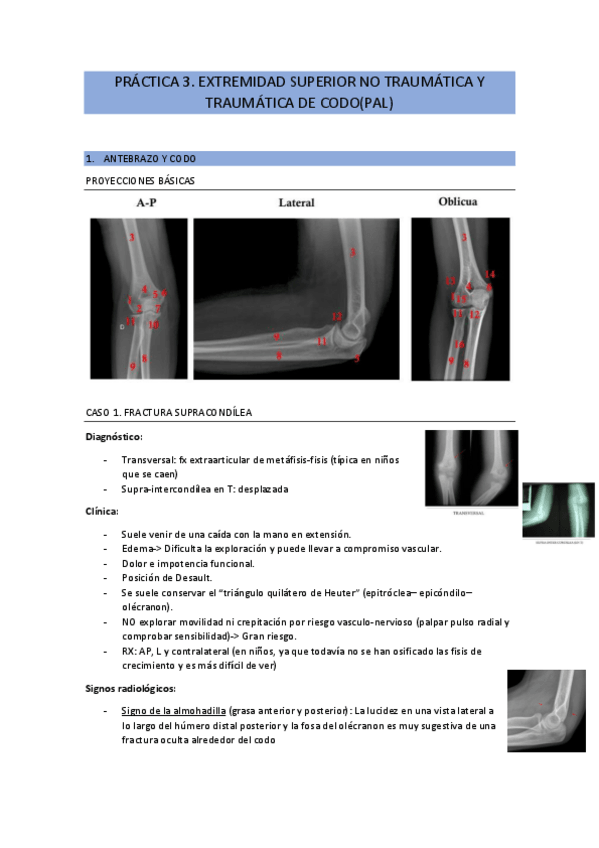

He publicado nuevos apuntes de 2º Patología y Enfoque Terapéutico del Aparato Locomotor: practica-3.-ext.-superior-no-traumatica-y-traumatica-de-codo-pal.pdf